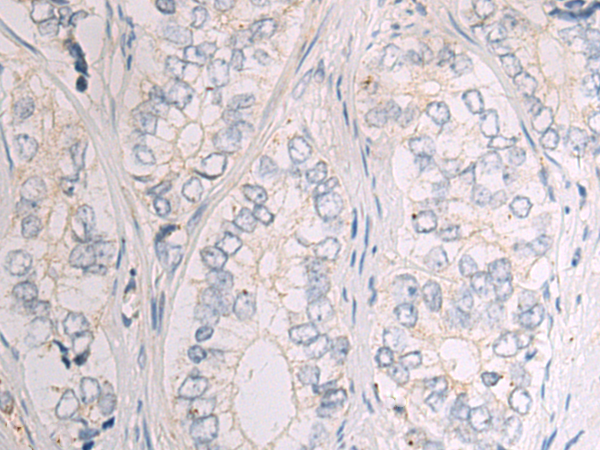

分类: 科研抗体货号: P06879别名: CTLO; HAMSV; HRAS1; RASH1; p21ras; C-H-RAS; H-RASIDX; C-BAS/HAS; C-HA-RAS1应用: WB,IHC反应种属: Human, Mouse, Rat

分类: 科研抗体货号: P06877别名: HD7; HD9; HD7b; HDAC; HDRP; MITR; HDAC7; HDAC7B; HDAC9B; HDAC9FL应用: IHC反应种属: Human, Mouse

分类: 科研抗体货号: P06922别名:应用: IHC反应种属: Human

分类: 科研抗体货号: P06873别名: B7-H; B7H1; PDL1; PD-L1; hPD-L1; PDCD1L1; PDCD1LG1应用: WB,IHC反应种属: Human